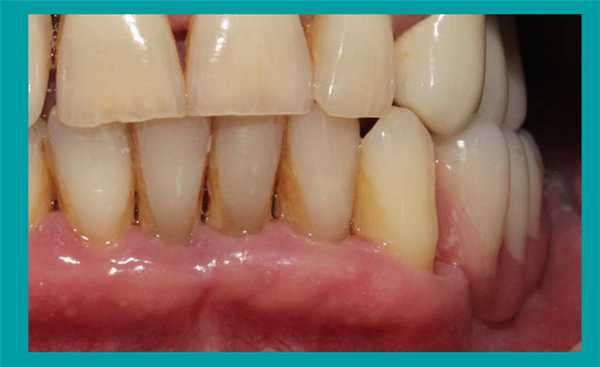

55-летняя женщина обратилась за стоматологической помощью по поводу нынешнего неудовлетворительного состояния ее зубов. Предыдущий стоматолог посоветовал ей провести экстракцию всех безнадежных зубов, но больной при этом было не весьма комфортно осознавать, что ей в дальнейшем все время придется использовать полный съемный протез. В ходе клинического осмотра были обнаружены симптомы умеренного и тяжелого пародонтита, множественные кариозные поражения, а также имеющиеся дефектные реставрации. У пациентки наблюдалось нарушение индивидуальной высоты межчелюстного соотношения, в области отдельных фронтальных зубов прогрессировал феномен Попова-Годона, но, в то же время, передние зубы обеспечивали адекватную поддержку тканям губ (фото 1).

Фото 1. Клинический случай №1: вид зубных рядов с ретрактором.